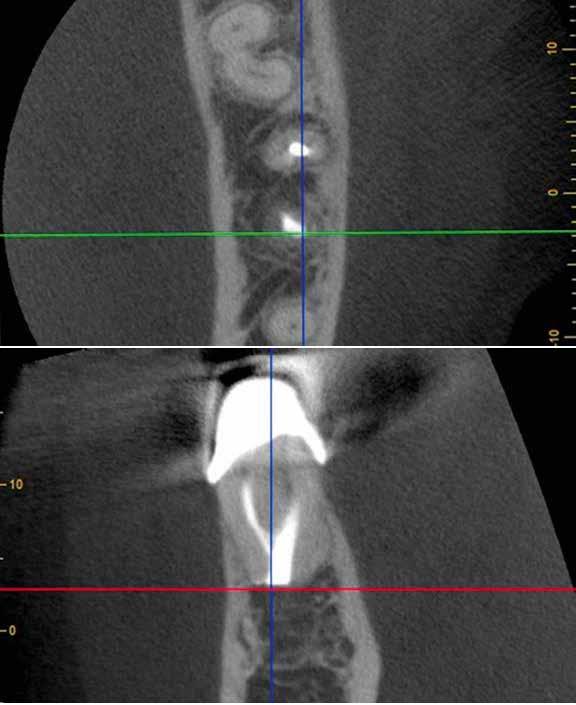

A fogszabályzó kezelések egyik legfontosabb célja, hogy elérjük a lehető legharmonikusabb interokkluzális fogérintkezéseket, továbbá az állcsont relációs helyzetének frontális és szaggitális síkban is megfelelőnek kell lennie. A fogszabályzás befejezésekor a fogpozícióknak nem orthodonciai, hanem protetikai szempontok szerint kell ideálisnak lenniük. Az Invisalign ClinCheck szoftver (Align Technology) segítségével a protetikus az orthodontussal együtt meg tudja határozni azokat a végső fogpozíciókat, amelyek a lehető legjobb végeredmény biztosításához elengedhetetlenek. Bizonyos klinikai paramétereket, mint a fogak klinikai koronájának nagyságát, az egyes fogak fogíven belüli optimális pozícióját, a fogívek egymáshoz viszonyított helyzetét, a fogak között látható rések nagyságát, a frontfogak tengelyének dőlését, az overjet és overbite mértékét már a kezelések megkezdése előtt pontosan definiálni kell. Ezeket az adatokat viszont csak a tervezett végleges fogpótlás ismeretében lehet meghatározni, ezért van szükség az orthodontus és a protetikus szoros együttműködésére.